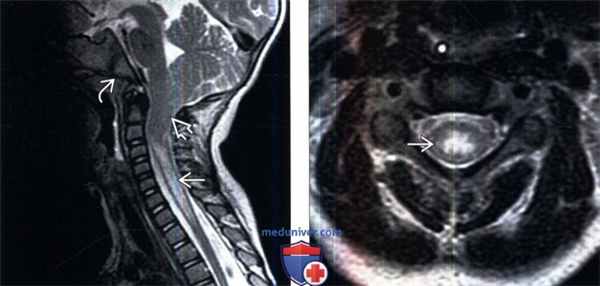

(Слева) Сагиттальный срез, Т1-ВИ (мальформация Киари 1): признаки значительной эктопии миндалин мозжечка ЕЯ при сохранения нормального положения тектальной пластинки и четвертого желудочка, что является характерными признаками мальформации Киари 1. Скат основания черепа также несколько укорочен. Обратите внимание на выраженные признаки отека паренхимы спинного мозга без явной его кистозной трансформации, что носит название «предкистозного состояния».

(Справа) Аксиальный срез, Т2-ВИ (мальформация Киари 1): центральный интрамедуллярный отек шейного отдела спинного мозга без признаков кистозной трансформации («предкистозное состояние»).